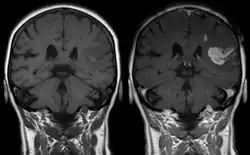

Die Magnetresonanztomographie (MRT) ist als bildgebendes Verfahren zu unempfindlich, um die Passage von Wirkstoffen in das Gehirn darzustellen. Völlig anders ist die Situation bei einer geschädigten Blut-Hirn-Schranke. In diesen Fällen spielt die kontrastmittelunterstützte MRT als diagnostisches Verfahren bei verschiedenen neurodegenerativen Erkrankungen und Krebserkrankungen im Bereich des Gehirns eine wichtige Rolle. Dies wird im Kapitel der mittelbar mit der Blut-Hirn-Schranke assoziierten Erkrankungen ausführlicher beschrieben.

Bereits kurz nach der Entwicklung von Gadopentetat-Dimeglumin (Gd-DTPA), dem ersten Kontrastmittel für die Kernspintomographie, 1984,[236] wurde das Potenzial der kontrastmittelverstärkten Magnetresonanztomographie für die Diagnose von lokalen Störungen der Blut-Hirn-Schranke erkannt.[237] Gd-DTPA ist als hochpolares Molekül viel zu hydrophil, um die gesunde Blut-Hirn-Schranke passieren zu können. Veränderungen an den Tight Junctions, wie sie beispielsweise durch Glioblastome ausgelöst werden, ermöglichen den parazellulären Transport dieses Kontrastmittels in das Interstitium. Dort verstärkt es durch die Wechselwirkung mit den Protonen des umgebenden Wassers den Kontrast und macht so die defekten Bereiche der Blut-Hirn-Schranke sichtbar. Da diese Blutgefäße für die Versorgung des Tumors zuständig sind und sich zu diesem in unmittelbarer Nachbarschaft befinden, lässt sich so das Ausmaß des Tumors darstellen.